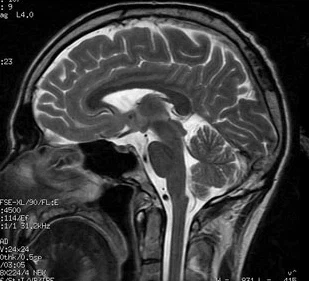

인체의 체표에 초음파를 발생시키면 음향저항의 차이(밀도나 경도의 차이)가 있는 조직에서 초음파가 반사되고, 반사된 메아리를 탐지하고 영상화하여 그 안의 내용물의 성상을 알아내는 것이 초음파진단법이며, 그 중에 연속파 또는 펄스파 초음파를 이용하여 동맥 또는 정맥이 좁아지거나 막힌 정도를 효과적으로 진단하는 검사입니다. 뿐만 아니라 혈류방향, 혈류의 속도 및 혈류량을 정확하게 측정할 수 있는 검사입니다.

인간의 귀에는 들리지 않는 높은 주파수의 진동을 나타내는 소리를 초음파라고 하며, 초음파를 이용한 비침습적인 검사이므로 검사 시 고통을 유발하거나 상처를 내지 않습니다.

혈관 영상 초음파 검사방법

혈관의 종·횡단면 영상을 통해 혈전이나 협착의 진행 정도와 Plaque(플라그)의 형태 등 혈관상태를 기록하며, 혈류의 파형과 혈류량 및 속도 등으로 혈류의 상태를 알 수 있습니다.